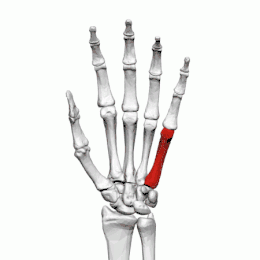

Cinquième métacarpien

Description

Le cinquième métacarpien est plus court que le quatrième métacarpien.